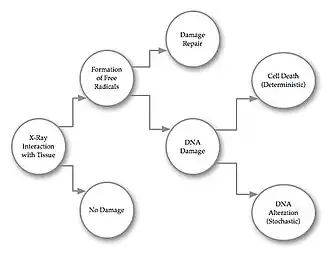

- Radiation damage to organic molecules occurs almost exclusively by free-radical interactions. Ionizing radiation exposure can produce free radicals in abundance through excitation processes. In cells, water is the most abundant source of radiation-produced hydrogen and hydroxyl free radicals. These can interact with molecules involved in cellular metabolism, for instance, and the normal function of the cell may become impaired. They can also interact with nucleic acid molecules which can result in cellular mutations or even cell death - see Figure 3.5. A broad range of damage can occur in genes and DNA double-strand breaks (DSBs) are considered to be the most likely trigger for cell killing, chromosome aberration formation and cancer induction. DSBs have been observed using immunofluorescence-based bioassays of venous blood samples taken from patients undergoing computed tomography (CT)[1] and percutaneous transluminal angioplasty (PTA)[2]. In addition, the use of contrast media has been found to enhance radiation damage to lymphocytes during CT[3].

- At the level of the individual, the radiation damage can be classified as either Deterministic or Stochastic. Deterministic damage generally refers to the killing of cells, while stochastic damage generally refers to cell modifications which do not impair the cell's capacity to reproduce.

- Cell death and replacement are natural processes which occur in tissue all the time. It can therefore be inferred that deterministic radiation damage is only of concern when the amount of cell death exceeds the replacement capacity of the tissue. Such damage can, as a result, be considered to occur only above a threshold dose. The value of this threshold has been found to be dependent on the type of tissue involved, ranging from red blood cells (relatively low radio-sensitivity), through to oesophageal epithelium and gastric mucosa (relatively high radio-sensitivity) to lymphocytes and ovarian follicular cells (very high sensitivity), for example. As a general guide, radio-sensitivity is dependent on the number of actively proliferating cells in the tissue and the length of the mitotic phase in the cell cycle. Furthermore, the degree of differentiation of the cells is inversely related to their radio-sensitivity. The severity of deterministic effects has been found to increase with radiation dose once this threshold has been exceeded. It should be noted, however, that these thresholds are rarely exceeded in well-managed clinical environments.

- In contrast, stochastic effects have no threshold dose. Here the probability, and not the severity, of damage is found to increase with dose. The onset of resultant diseases, e.g. leukaemia, solid tumour formation, caused by stochastic effects have been found to occur only after a latency period of several years or decades. Stochastic health risk is therefore substantially higher for paediatric radiography examinations than it is for the radiography of aged people, for example.

- The difference between the two effects can be considered to result because changes in single cells are sufficient to cause stochastic damage while changes in many cells are needed for deterministic effects to occur. Note that this implies that any dose of X-rays has a theoretical potential to cause cancer and that thresholds need to be exceeded before deterministic effects can occur.